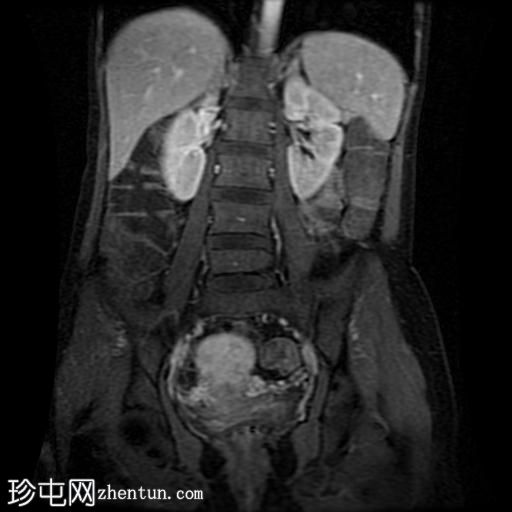

冠状位T2加权像

脂肪抑制

回肠末端及盆腔回肠肠袢可见长段肠壁增厚及强化,肠周血管丰富,呈“梳状征”,并可见明显的纤维脂肪浸润。

未见瘘管、积液、腹水或梗阻。

磁共振肠道造影(MRE)结果支持克罗恩病的诊断,显示远端及末端回肠以活动

性病

变为主,并可见明显的肠周血管。